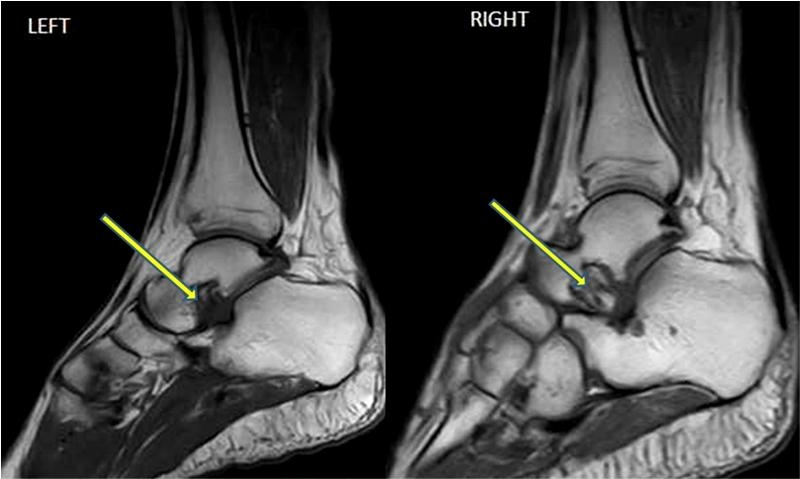

22. 족근동 증후군(Sinus tarsi syndrome)은 무엇이며, MRI 영상으로는 어떻게 보이는가?

족근동 증후군(Sinus tarsi syndrome)은 족근동 내부에 정상적인 지방 조직의 감소가 나타난다. 급성 또는 아급성기에는 염증으로 낮은 T1 신호와 높은 T2 신호가 나타난다. 만성의 경우에는 섬유증으로 낮은 T1과 T2 신호를 보인다. 환자는 발목의 위약감과 불안정성을 호소하는데, 족근동 위의 촉친할 수 있는 압통이 나타난다. 대부분의 경우는 특발성이지만, 몇몇의 환자는 발목의 내전 손상의 병력을 가진다. 족근동 증후군의 다른 경우들은 류마티스 관절염이나 통풍, 결절종(ganglion cyst)과 같은 염증 상황에서 나타난다.

△ 시상면 T1 강조 영상은 좌측의 족근동에서의 정상적인 지방 소멸로 인해 저강도로 나타남을 보여준다. 우측은 정상적인 영상

△ 시상면 T2 강조 영상에서는 고강도의 신호로 나타난다.